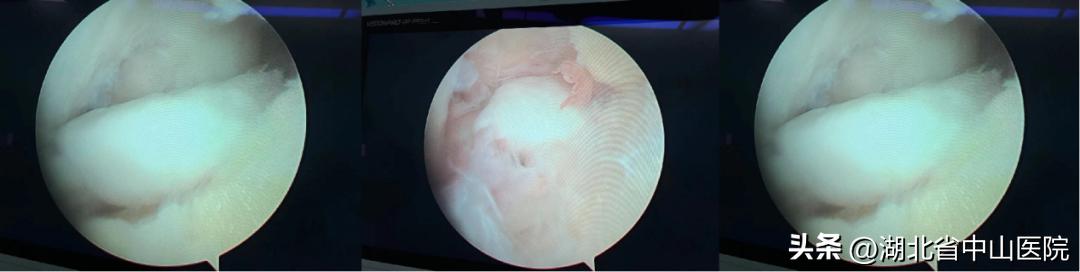

术中情况

手术不到半个小时就顺利结束,麻醉清醒后,王显勋指着盒子给余女士看:“这就让你膝关节卡住的‘罪魁祸首’。”只见盒子里装着两枚乳白色卵石样的游离体,其中一枚足有大拇指甲盖大小,另一枚也有豌豆大小。